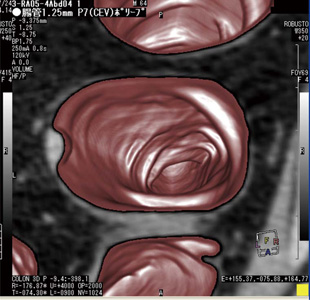

図4に展開表示モードを示す。大腸を切り開いた標本のような画像を表示するモードである。この表示モードは,大腸内壁を1画面に表示することで,ポリープなどの存在位置の確認を容易にする利点を持つ1),2)

また,CT Colonoscopyの展開表示モードは,大腸径に応じて展開画像の横方向の長さを調節している。これにより縦横比が均等となり,ポリープなどの突起物が歪むことなく,実際の形状に近い形状で表示される。

そのほか,大腸の曲率に応じて経路に対する断面の角度を変化させながら展開画像を作成する画像歪み低減補正や,ポリープなどの突起物が画像の上下に分割されて表示されるのを防ぐために,展開画像の上端および下端で一部の領域を重複させて表示させる機能も搭載している。

図4 展開表示モード